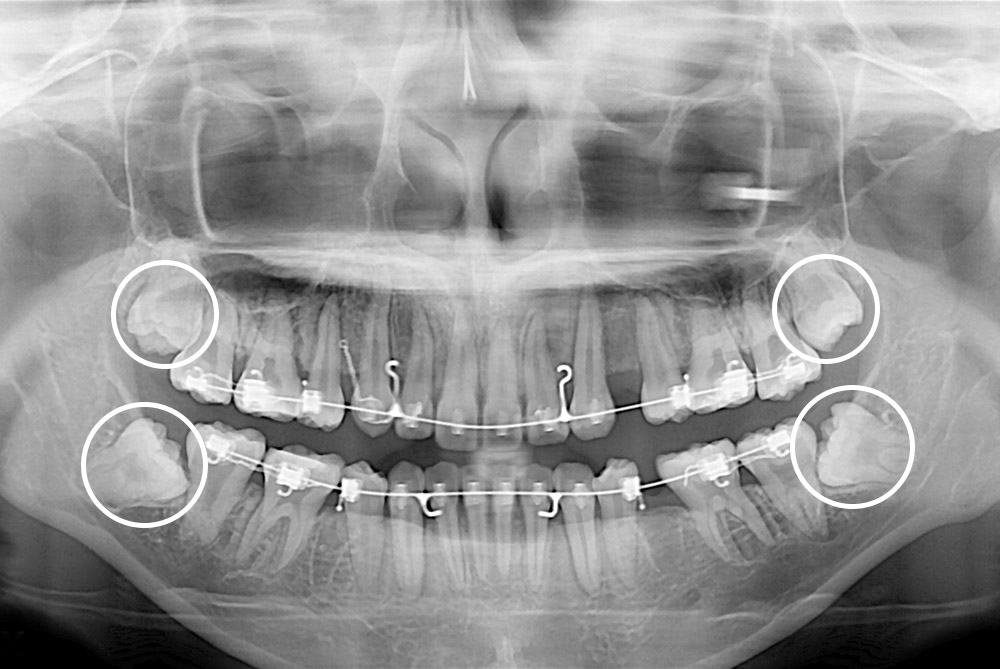

[사랑니] 매복 사랑니 발치

치료전 : 2018-11-20

치료후 : 2022-11-02

세종치과는 구강악안면외과학 박사이신 원장님이 발치하는 치과입니다.